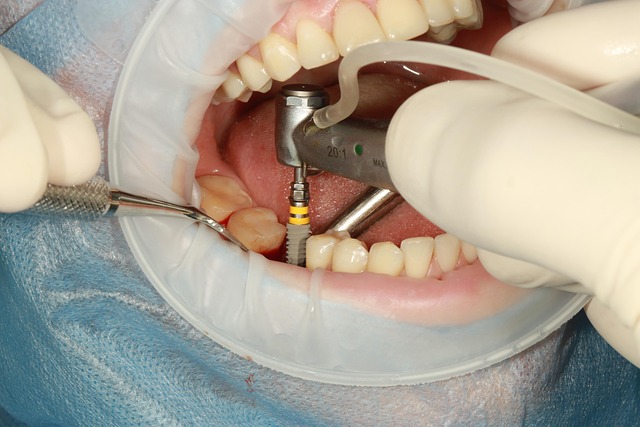

임플란트는 단순한 치과 치료가 아닌, 오랜 시간 함께할 인공치아를 심는 중요한 시술입니다. 하지만 많은 분들이 시술 전 가장 고민하는 부분은 바로 비용과 보험 적용 여부일 텐데요. 저도 최근에 임플란트 시술을 고민하며 여러 곳을 알아봤고, 실제로 상담도 받아본 경험을 바탕으로 정보를 공유해드리려고 합니다.